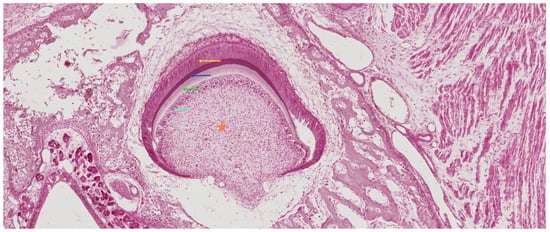

3.4. The Crown Stage—Apposition

3.5. Root Formation